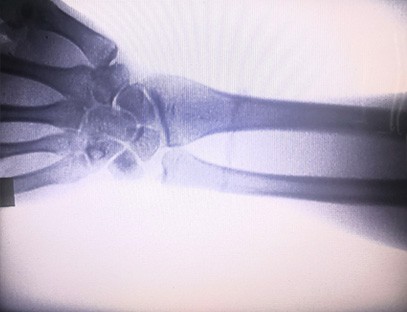

विशेषज्ञता:आर्थोपेडिक क्लीनिकों की जरूरतों के लिए डिज़ाइन किया गया, विशेष रूप से उपयुक्तएक्स-रे इमेजिंगहाथ, कलाई, कोहनी, कंधे, घुटने, टखने आदि जैसे अंगों का।

स्पष्ट इमेजिंग:उन्नत डिजिटल इमेजिंग प्रौद्योगिकी का उपयोग उच्च गुणवत्ता वाली एक्स-रे छवियां प्रदान करने के लिए किया जाता है, जिससे डॉक्टरों को स्थिति का सटीक निदान करने में मदद मिलती है।

एक पोर्टेबल एक्स-रे मशीनकम विकिरण खुराक वाला, बहुत सुरक्षित पोर्टेबल उपकरण है जो विकिरण जोखिम को कम करते हुए उच्च गुणवत्ता वाली छवियां प्राप्त कर सकता है। यह बड़े अस्पताल के उपकरणों की कमियों की भरपाई करता है और इसे किसी भी समय इधर-उधर ले जाया जा सकता है। विशेष रूप से अपर्याप्त बजट और छवियों के लिए कम आवश्यकताओं वाली इकाइयों और व्यक्तियों के लिए उपयुक्त है। हमारी नई पीढ़ी की एक्स-रे मशीन 10 इंच की हाई-डेफिनिशन बड़ी स्क्रीन से लैस है, जिसमें देखने के कोण की एक बड़ी रेंज है और यह पूरी हथेली के आर-पार देख सकती है, जिसमें फ्रैक्चर, डिस्लोकेशन, गठिया और हड्डी के ट्यूमर शामिल हैं। इसे ऑर्थोपेडिक फिल्मों को प्रिंट करने के लिए फिल्म प्रिंटर से जोड़ा जा सकता है और इसका उपयोग औद्योगिक उत्पादन और परीक्षण के लिए भी किया जा सकता है। डार्करूम, प्रत्यक्ष परिप्रेक्ष्य, वास्तविक समय अवलोकन की कोई आवश्यकता नहीं है। इस मशीन में एक उच्च-रिज़ॉल्यूशन इमेजिंग सिस्टम है जो किसी भी हड्डी की संरचना की छवियों को बहुत स्पष्ट रूप से कैप्चर कर सकता है। चिकित्सा, पालतू, औद्योगिक, इलेक्ट्रॉनिक उत्पाद निर्माताओं, निरीक्षण और रखरखाव विभागों और अनुसंधान प्रयोगशालाओं के लिए सर्वोत्तम एक्स-रे परीक्षण उपकरण और समाधान प्रदान करना।